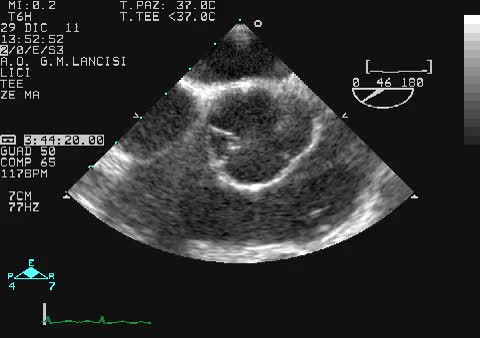

Valvola aortica quadricuspide

Moreno Cecconi